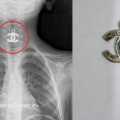

2022-03-24 17:54:01

4 տարեկան երեխայի կերակրափողից հեռացվել է մետաղյա կախազարդ. «Սուրբ Աստվածամայր» ԲԿ